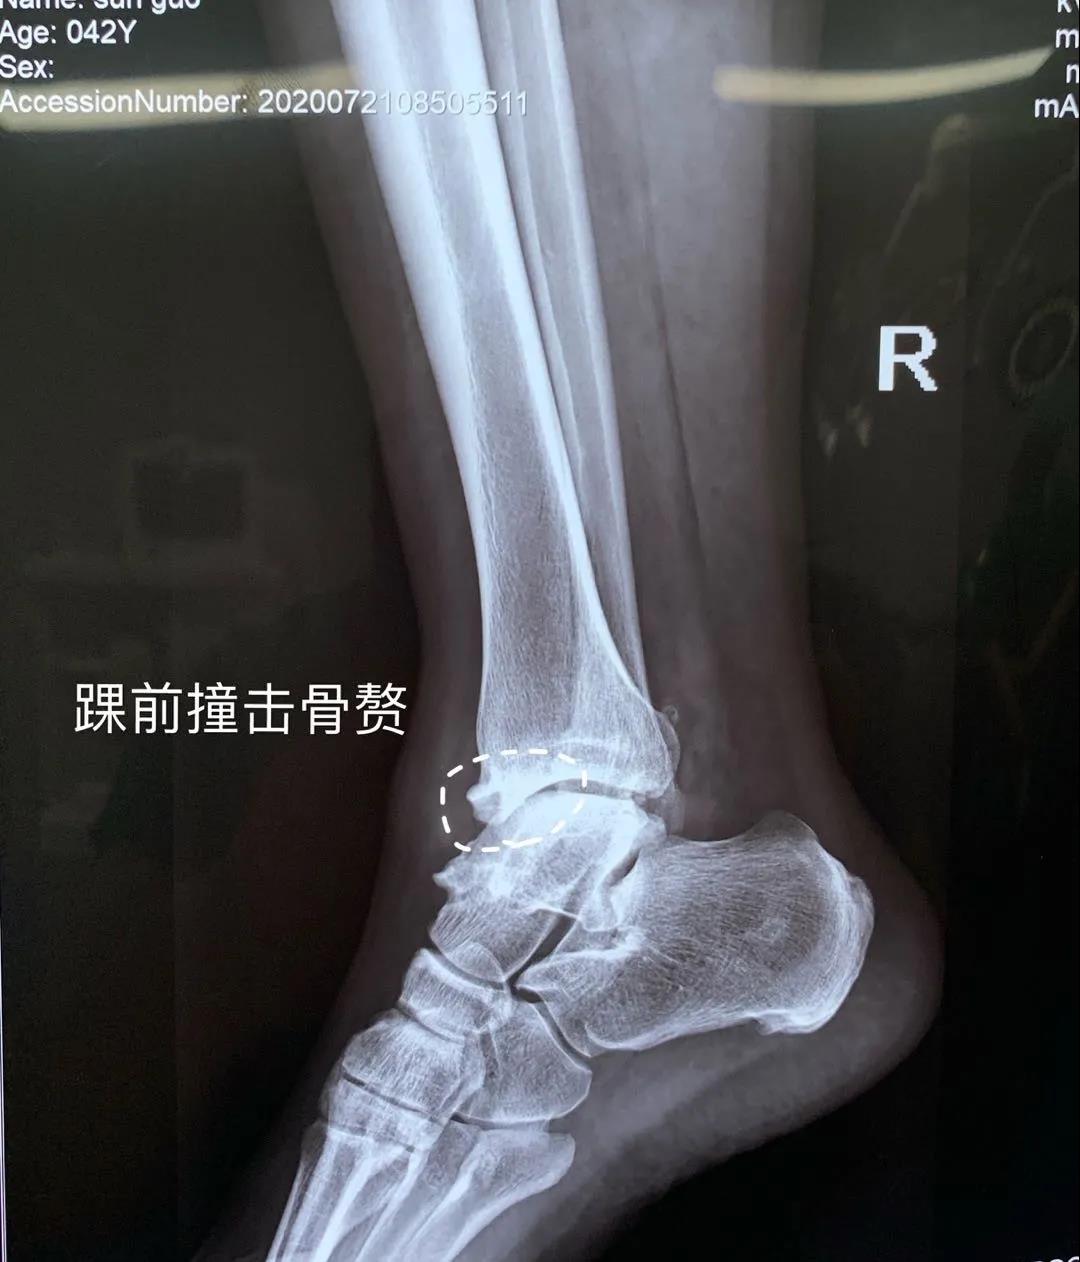

近日,醫(yī)院骨二科成功治療一位關(guān)節(jié)反復(fù)疼痛病人。患者李某,男,42歲,踝關(guān)節(jié)外傷導(dǎo)致外側(cè)韌帶損傷踝關(guān)節(jié)不穩(wěn),長(zhǎng)期沒有及時(shí)治療導(dǎo)致踝關(guān)節(jié)骨關(guān)節(jié)炎的發(fā)生。患者踝關(guān)節(jié)疼痛不能長(zhǎng)距離行走這是術(shù)前應(yīng)力位片提示踝關(guān)節(jié)距骨傾斜,踝關(guān)節(jié)踝前撞擊綜合癥,給予踝關(guān)節(jié)鏡下關(guān)節(jié)腔清理,骨贅切除,并給予外側(cè)韌帶重建恢復(fù)關(guān)節(jié)穩(wěn)定性。目前,患者手術(shù)后的踝關(guān)節(jié)穩(wěn)定,功能恢復(fù)良好,即將康復(fù)出院。